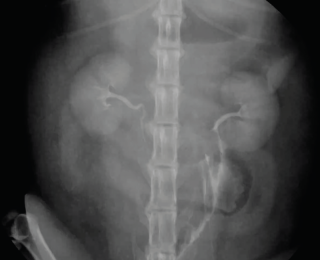

Urinary tract rupture can also occur with pelvic injury. A palpable bladder and the ability to urinate does not exclude urinary tract trauma (Aumann 1998). Baseline blood work indicating azotaemia and hyperkalaemia and a point-of-care ultrasound indicating abnormal abdominal fluid can help confirm a uroabdomen. Abdominocentesis and fluid analysis can provide further confirmation: in one case series the mean ratio of serum to peritoneal effusion for creatinine and potassium was 2:1 and 1.9:1 respectively (Aumann 1998). The perineal area should also be assessed for subcutaneous leakage from caudal urethral ruptures, but skin necrosis may take 24-48 hours to develop. A contrast study should be performed if there is confirmation of rupture or any uncertainty of patency (Figures 11 and 12). In the author’s institute, an intravenous urethrogram is generally performed prior to a retrograde urethrogram to confirm the ureters are patent.